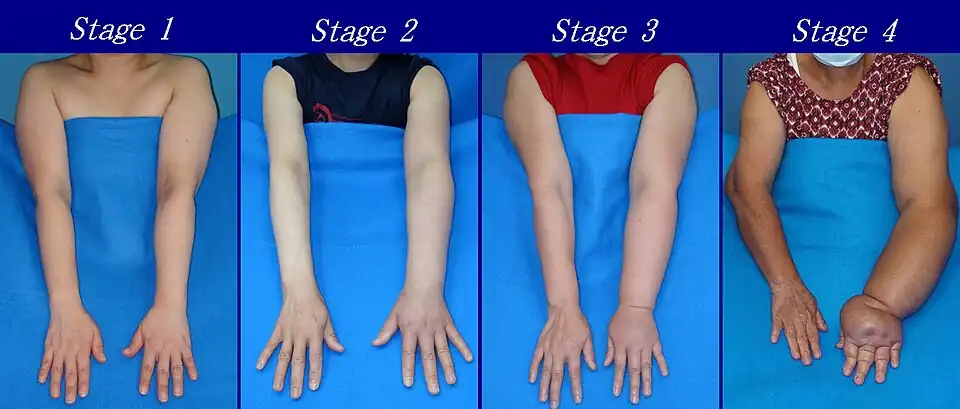

The International Society of Lymphology (ISL) Staging System is based solely on subjective symptoms, making it prone to substantial observer bias. Imaging modalities have been suggested as useful adjuncts to the ISL staging to clarify the diagnosis, such as Cheng's Lymphedema Grading tool, which assesses the severity of extremity lymphedema based on objective limb measurements and provides appropriate options for management.[39][40][41]

As described by the Fifth WHO Expert Committee on Filariasis,[43][44] and endorsed by the American Society of Lymphology,[45] the staging system helps to identify the severity of lymphedema. With the assistance of medical imaging, such as MRI or CT, staging can be established by the physician, and therapeutic or medical interventions may be applied:

- Stage 0: The lymphatic vessels have sustained some damage that is not yet apparent. Transport capacity is sufficient for the amount of lymph being removed. Lymphedema is not present.

- Stage 1 : Swelling increases during the day and disappears overnight as the patient lies flat in bed. Tissue is still at the pitting stage: when pressed by the fingertips, the affected area indents and reverses with elevation. Usually, upon waking in the morning, the limb or affected area is normal or almost normal in size. Treatment is not necessarily required at this point.

- Stage 2: Swelling is not reversible overnight, and does not disappear without proper management. The tissue now has a spongy consistency and is considered non-pitting: when pressed by the fingertips, the affected area bounces back without indentation. Fibrosis found in Stage 2 lymphedema marks the beginning of the hardening of the limbs and increasing size.

- Stage 3: Swelling is irreversible and usually the limb(s) or affected area becomes increasingly large. The tissue is hard (fibrotic) and unresponsive; some patients consider undergoing reconstructive surgery, called "debulking". This remains controversial, however, since the risks may outweigh the benefits and further damage done to the lymphatic system may make the lymphedema worse.

- Stage 4: The size and circumference of the affected limb(s) become noticeably larger. Bumps, lumps, or protrusions (also called knobs) on the skin begin to appear.